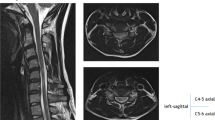

We report on a 30-year-old female whose onset presented as unilateral muscle atrophy of the right hand in her teens. Despite conservative treatment using a cervical collar, she developed prolonged bilateral muscle atrophy, sensory disturbance and spastic gait, along with bladder and rectal disturbances. Her hands were frozen into a ‘claw-like’ gesture and her intrinsic muscles were highly atrophic. She was unable to unclench her hands. Although the space available for the spinal cord was large, the spinal cord was highly atrophic. She had local kyphosis with a large (61°) flexion range of motion. During flexion the spinal cord was stretched, resulting in contact with the posterior wall of the vertebrae. Posterior fusion surgery was performed to prevent progression of the myelopathy. After surgery, she gained mild improvement in both muscle strength and her hand’s movement. However, her spastic gait and muscle atrophy remained.